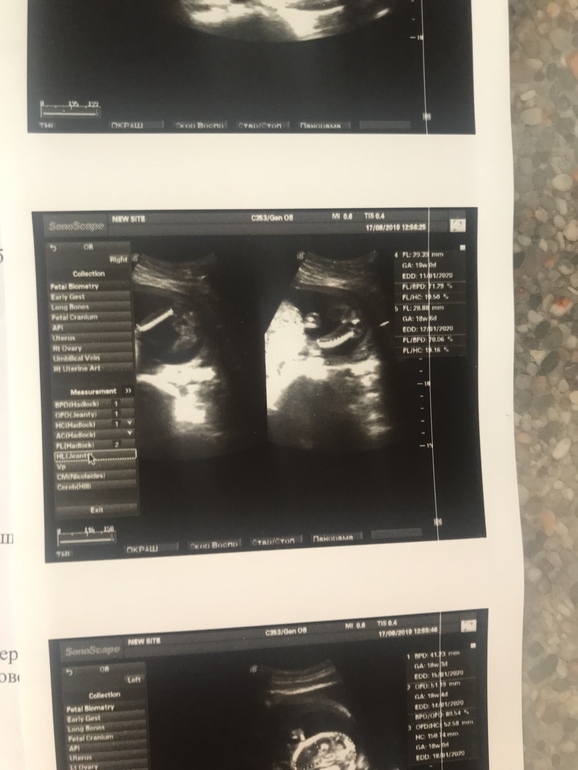

Тесты, ждем день Хдевочки,ходили с мужем на узи. 18 недель , сказали,что девочка, как думаете не ошиблась врач? потому что по всем приметам- у нас мальчик. хотелось бы знать ,чтобы уже и с ремонтом определиться и с вещами для крошки )

Ради интереса почитала приметы. По ним у нас на 90% девочка, хотя уже 3 УЗИ сказали мальчик, ну и стоп кадр специально мне сделали))))